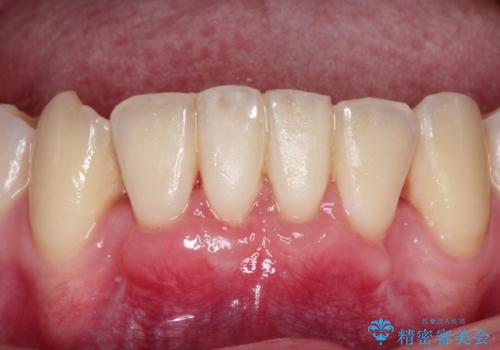

下顎前歯の歯肉退縮 結合組織を用いた根面被覆

- 歯肉退縮を主訴に来院された患者様です。

口蓋から結合組織を採取して、根面被覆を行いました。

十分な根面被覆を達成で患者様にも満足していただけました。